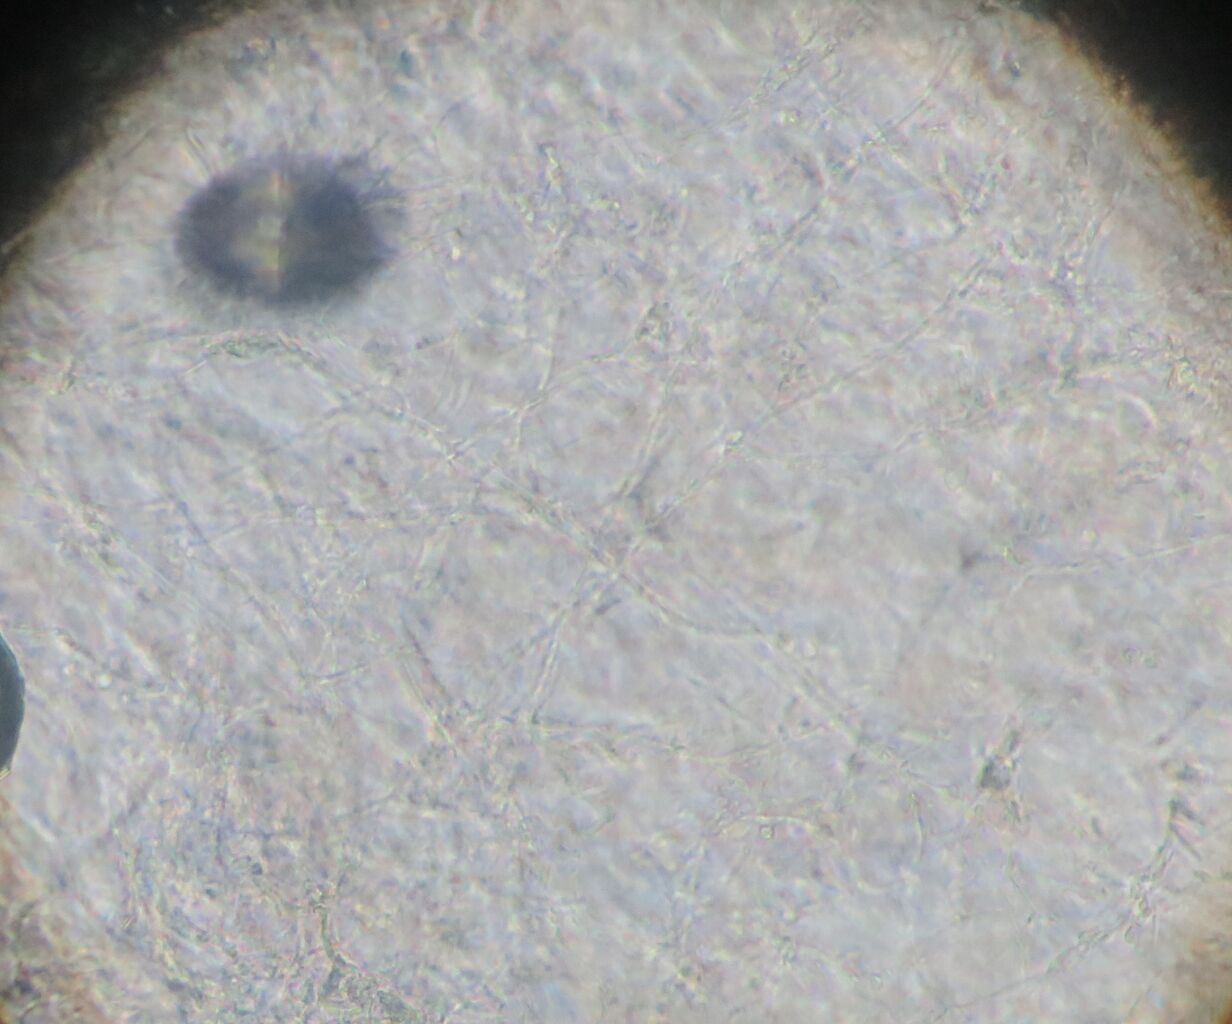

写真の様に皮膚が壊れて深い部分まで損傷している場合に用います。

肉芽や上皮の再生を促してくれる外用薬です。